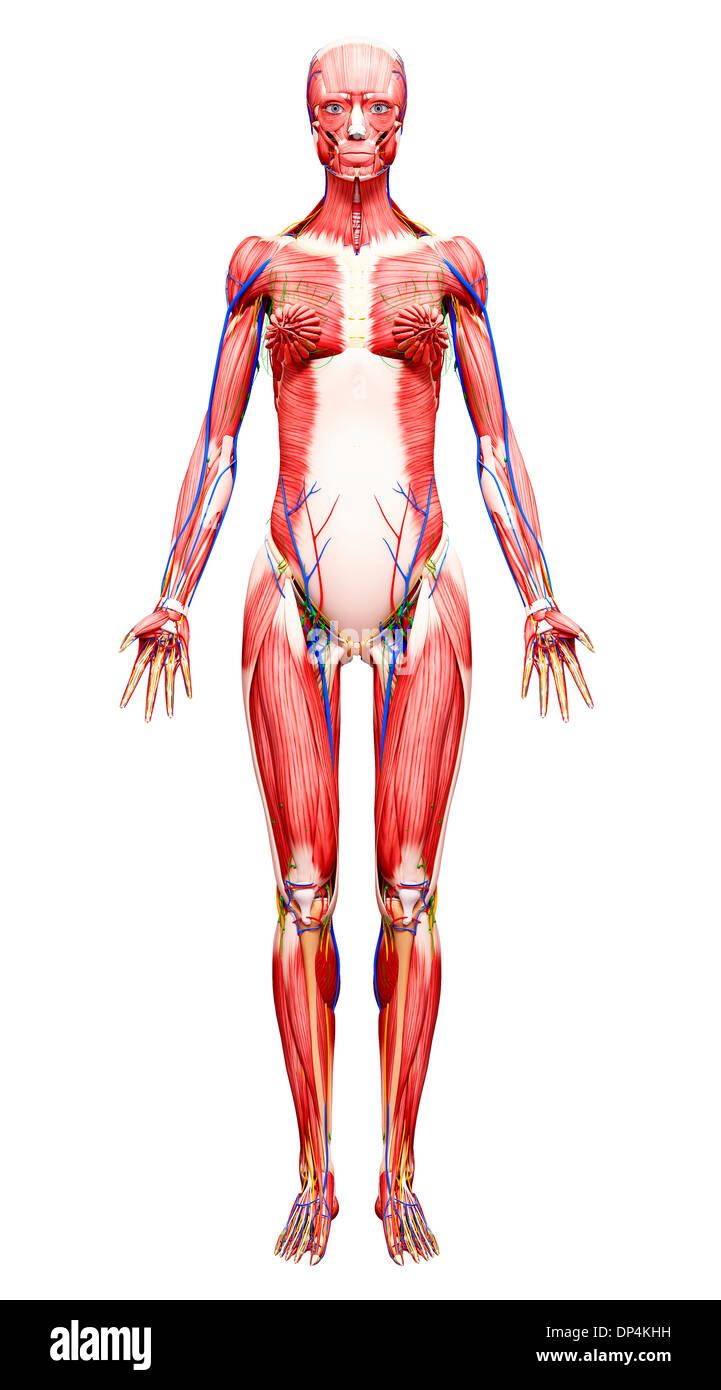

, Artwork Banque D'Imageshttps://www.alamyimages.fr/image-license-details/?v=1https://www.alamyimages.fr/artwork-image65256733.html

, Artwork Banque D'Imageshttps://www.alamyimages.fr/image-license-details/?v=1https://www.alamyimages.fr/artwork-image65256733.htmlRFDP4KHH–, Artwork